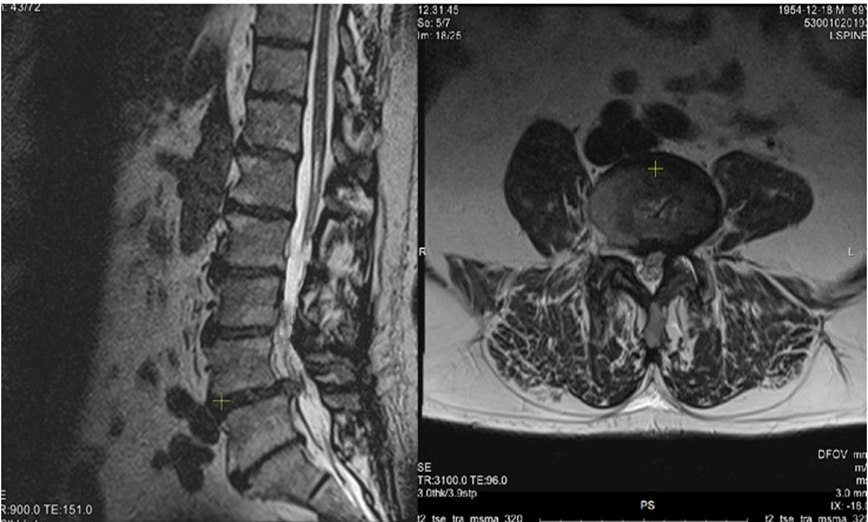

A 71-year-old man presented with a progressive chronic low back pain radiating to the left buttock, lateral thigh, leg, and leg in 2022. The pain was described as dull and aching in the lumbar region, with sharp radicular exacerbations, especially on the left side. Symptoms were aggravated by standing and lumbar extension and relieved by sitting or forward flexion. The patient reported numbness and tingling along the same distribution, causing difficulty in walking. Walking distance was progressively limited due to pain and heaviness in both lower limbs, improving with rest or forward bending, suggestive of neurogenic claudication. On examination, lumbar lordosis was reduced, with tenderness and at the L4-L5 level, and paraspinal muscle spasm. Lumbar motion was restricted, with painful arc and instability on extension. Straight leg raising was positive on the left at 40°, right at 45°. Neurological assessment revealed pain an paresthesia is both L5 myotomes (mostly in left), preserved deep tendon reflexes. His pre-operative Visual Analogue Scale (VAS) score was 8, and the Oswestry Disability Index (ODI) was 82 %. Pre-operative Magnetic Resonance Imaging (MRI) and CT Scans showed a lowgrade (Meyerding I) L4 spondylolisthesis with a mediolateral, predominantly left-sided L4-L5 disc herniation causing foraminal and central stenosis (Figure 1). L4-L5 Minimally Invasive Spine Surgery (MISS) Transforaminal Lumbar Interbody Fusion (TLIF) with modular percutaneous screws was performed at our institution, including L4 discectomy and the insertion of a PEEK cage filled with bone graft, Post-operatively his condition improved dramatically: at the moment of discharge at 3rd postoperative day his VAS was 2-3 and ODI 8 % at six-month follow-up, with Bridwell fusion grade II.

Figure 1: Shows spondylolisthesis and an L4 mediolateral disc herniation causing bilateral, mostly left sided foraminal stenosis.